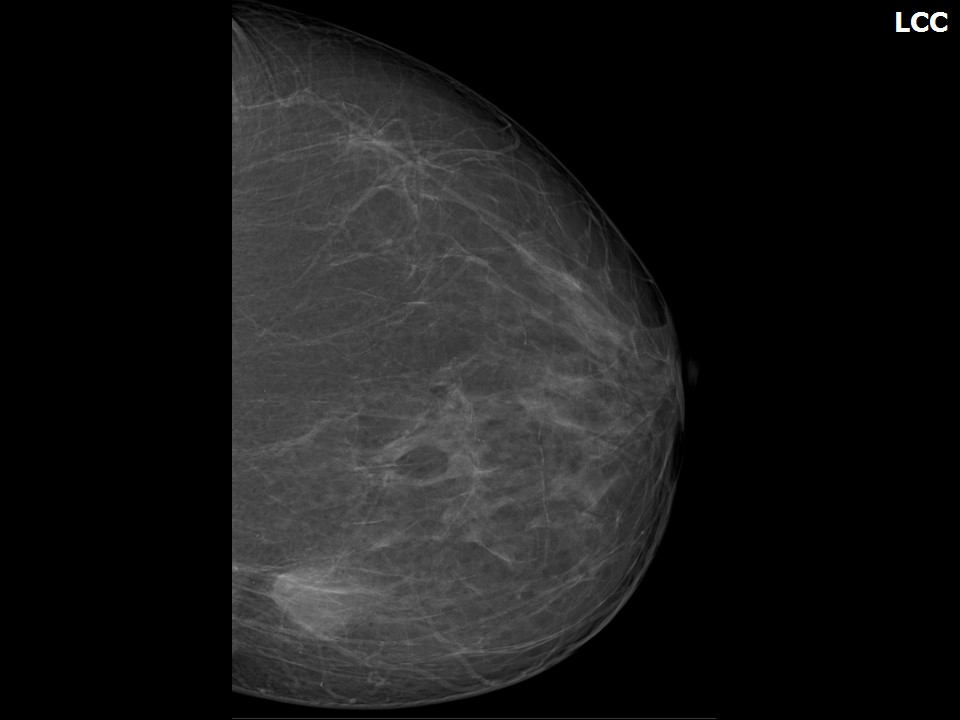

Аномалии молочной железы: медицинские примеры и визуализация